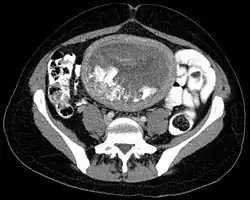

Hydatidiform mole on CT, sagittal view

Hydatidiform mole on CT, axial view

The diagnosis is strongly suggested by ultrasound (sonogram), but definitive diagnosis requires histopathological examination. On ultrasound, the mole resembles a bunch of grapes ("cluster of grapes" or "honeycombed uterus" or "snow-storm").[14] There is increased trophoblast proliferation and enlarging of the chorionic villi, and angiogenesis in the trophoblasts is impaired.[15]